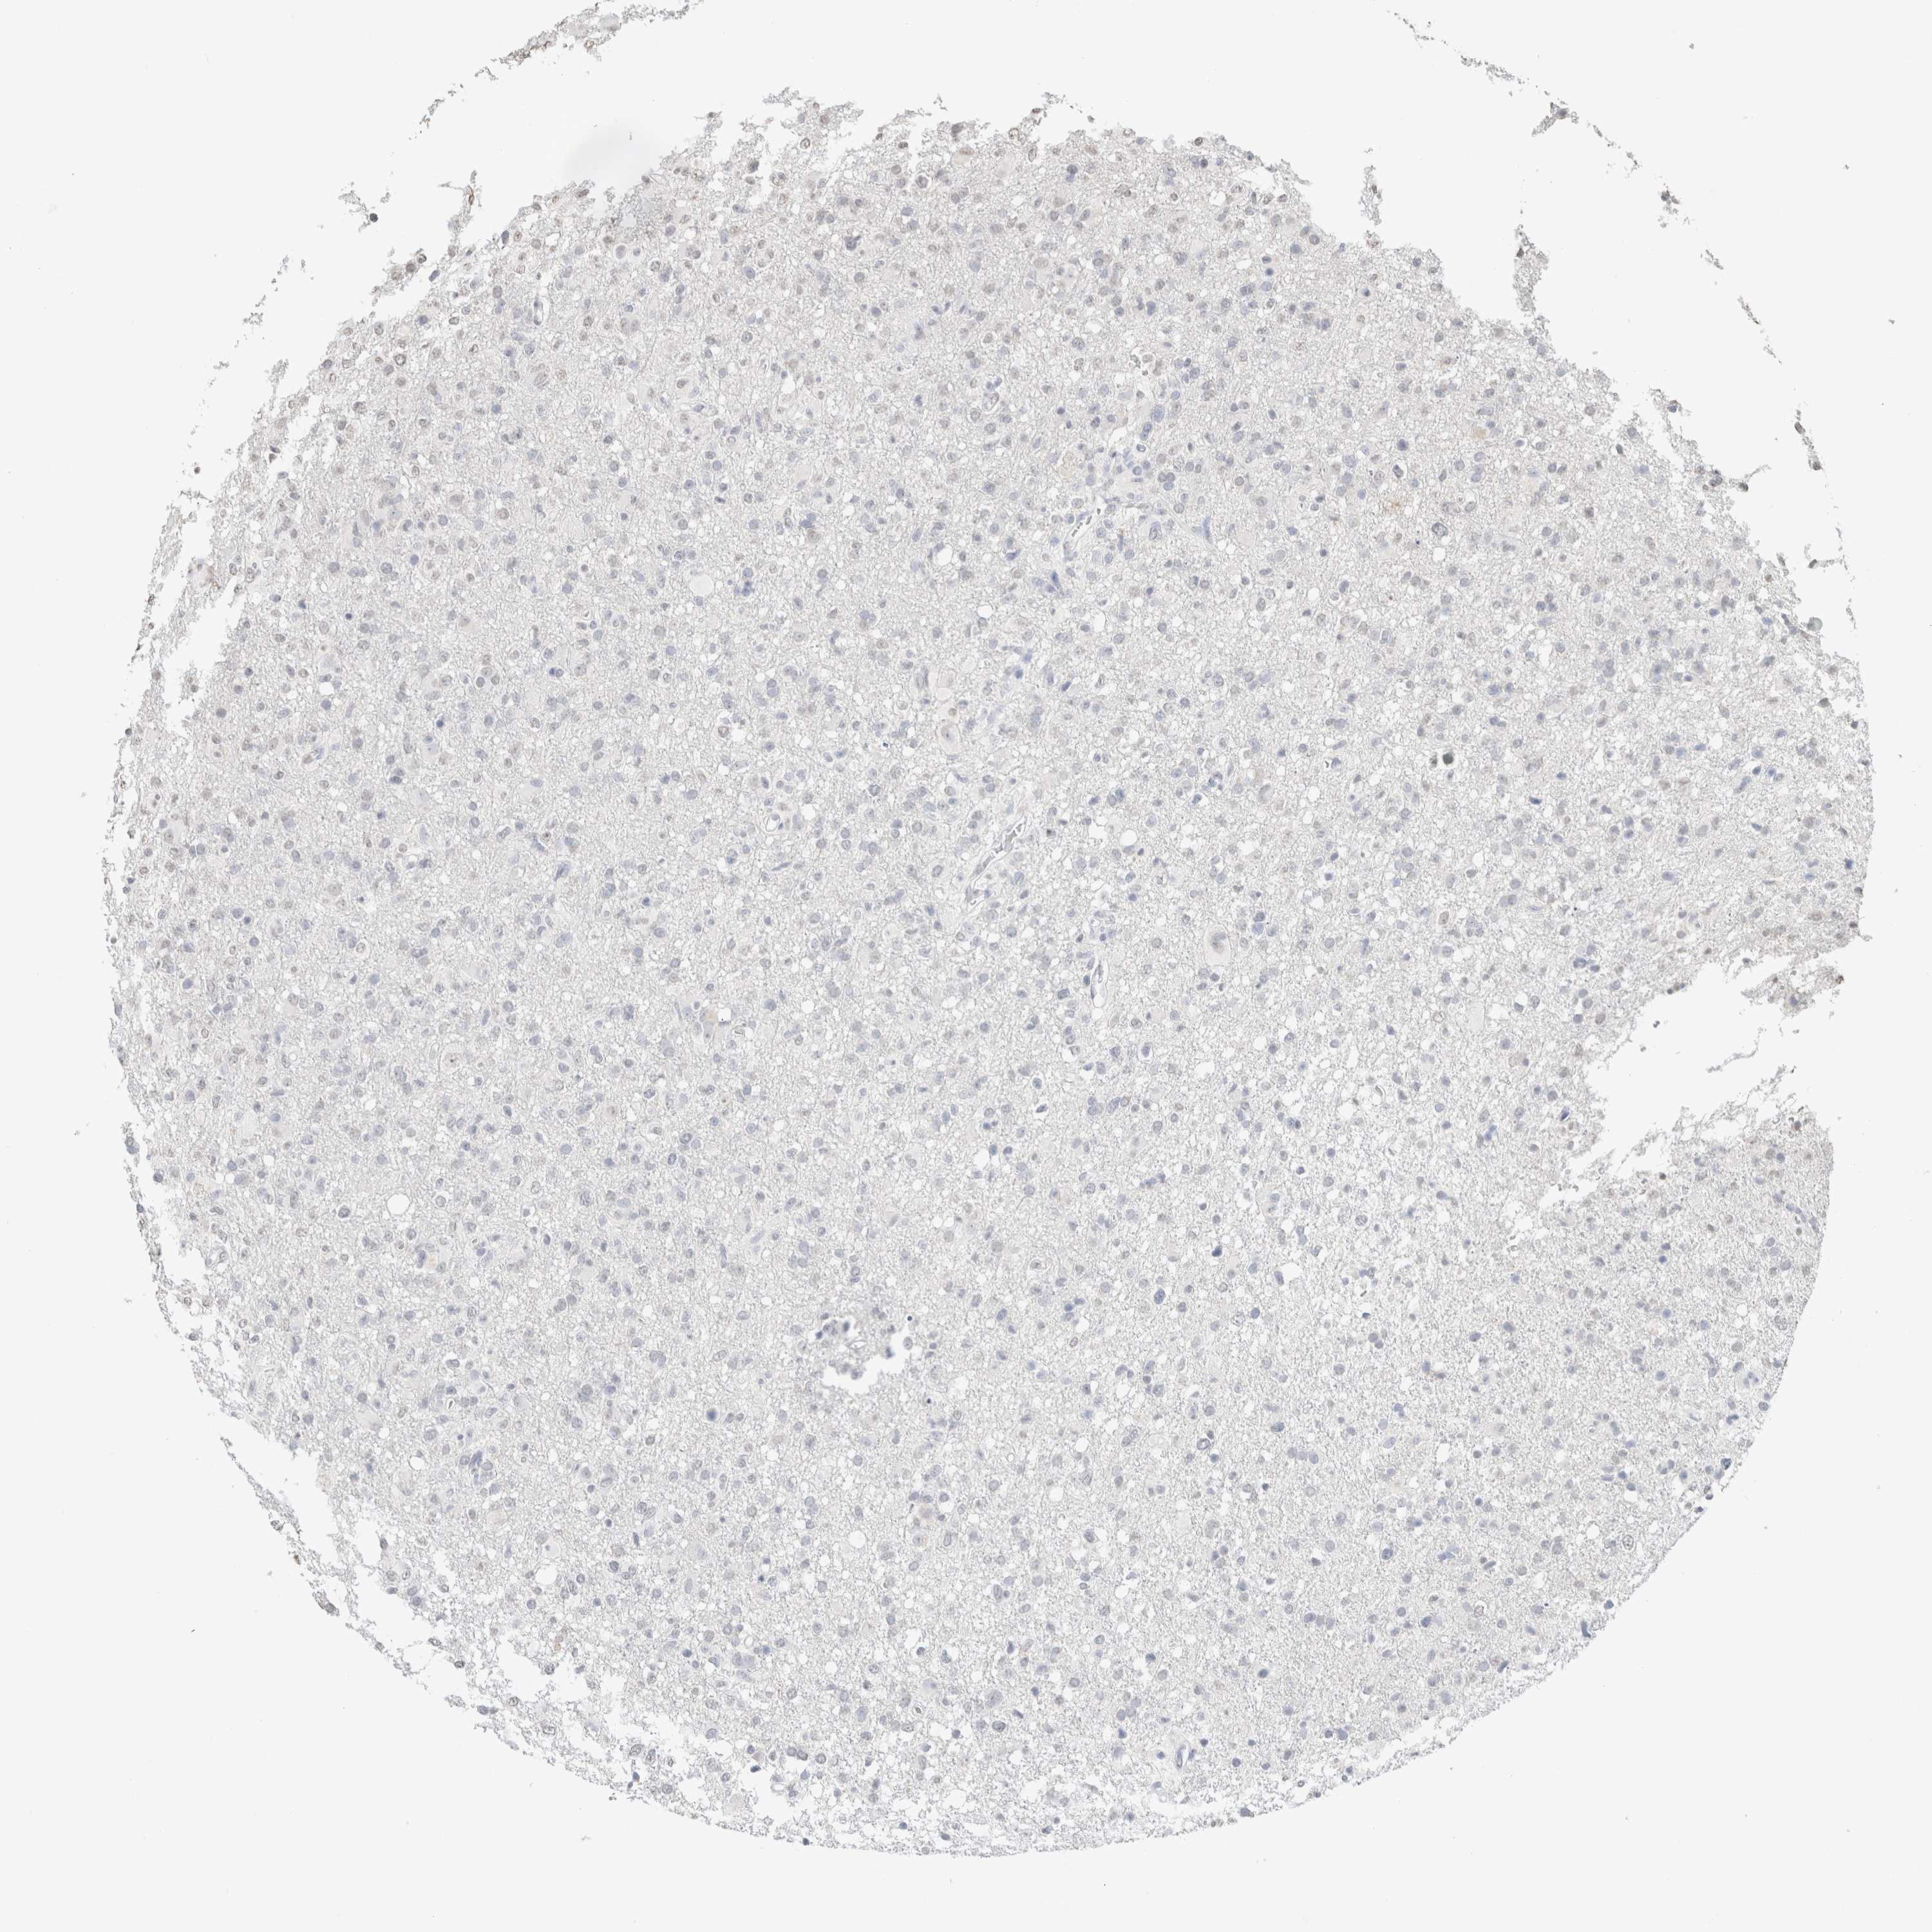

GLIOMA - Protein expressioni

A mouse-over function shows sample information and annotation data. Click on an image to view it in a full screen mode. Samples can be filtered based on level of antibody staining by selecting one or several of the following categories: high, medium, low and not detected. The assay and annotation is described here.

Note that samples used for immunohistochemistry by the Human Protein Atlas do not correspond to samples in the TCGA dataset.

Antibody stainingi

Antibody staining in the annotated cell types in the current human tissue is reported as not detected, low, medium, or high, based on conventional immunohistochemistry profiling in selected tissues. This score is based on the combination of the staining intensity and fraction of stained cells.

Each image is clickable and will lead to virtual microscopy that enables deeper exploration of all samples and also displays staining intensity scores, fraction scores and subcellular localization as well as patient and tissue information for each sample.

Antibody HPA050092

Antibody CAB025368

Glioma, malignant, High grade

Glioma, malignant, Low grade